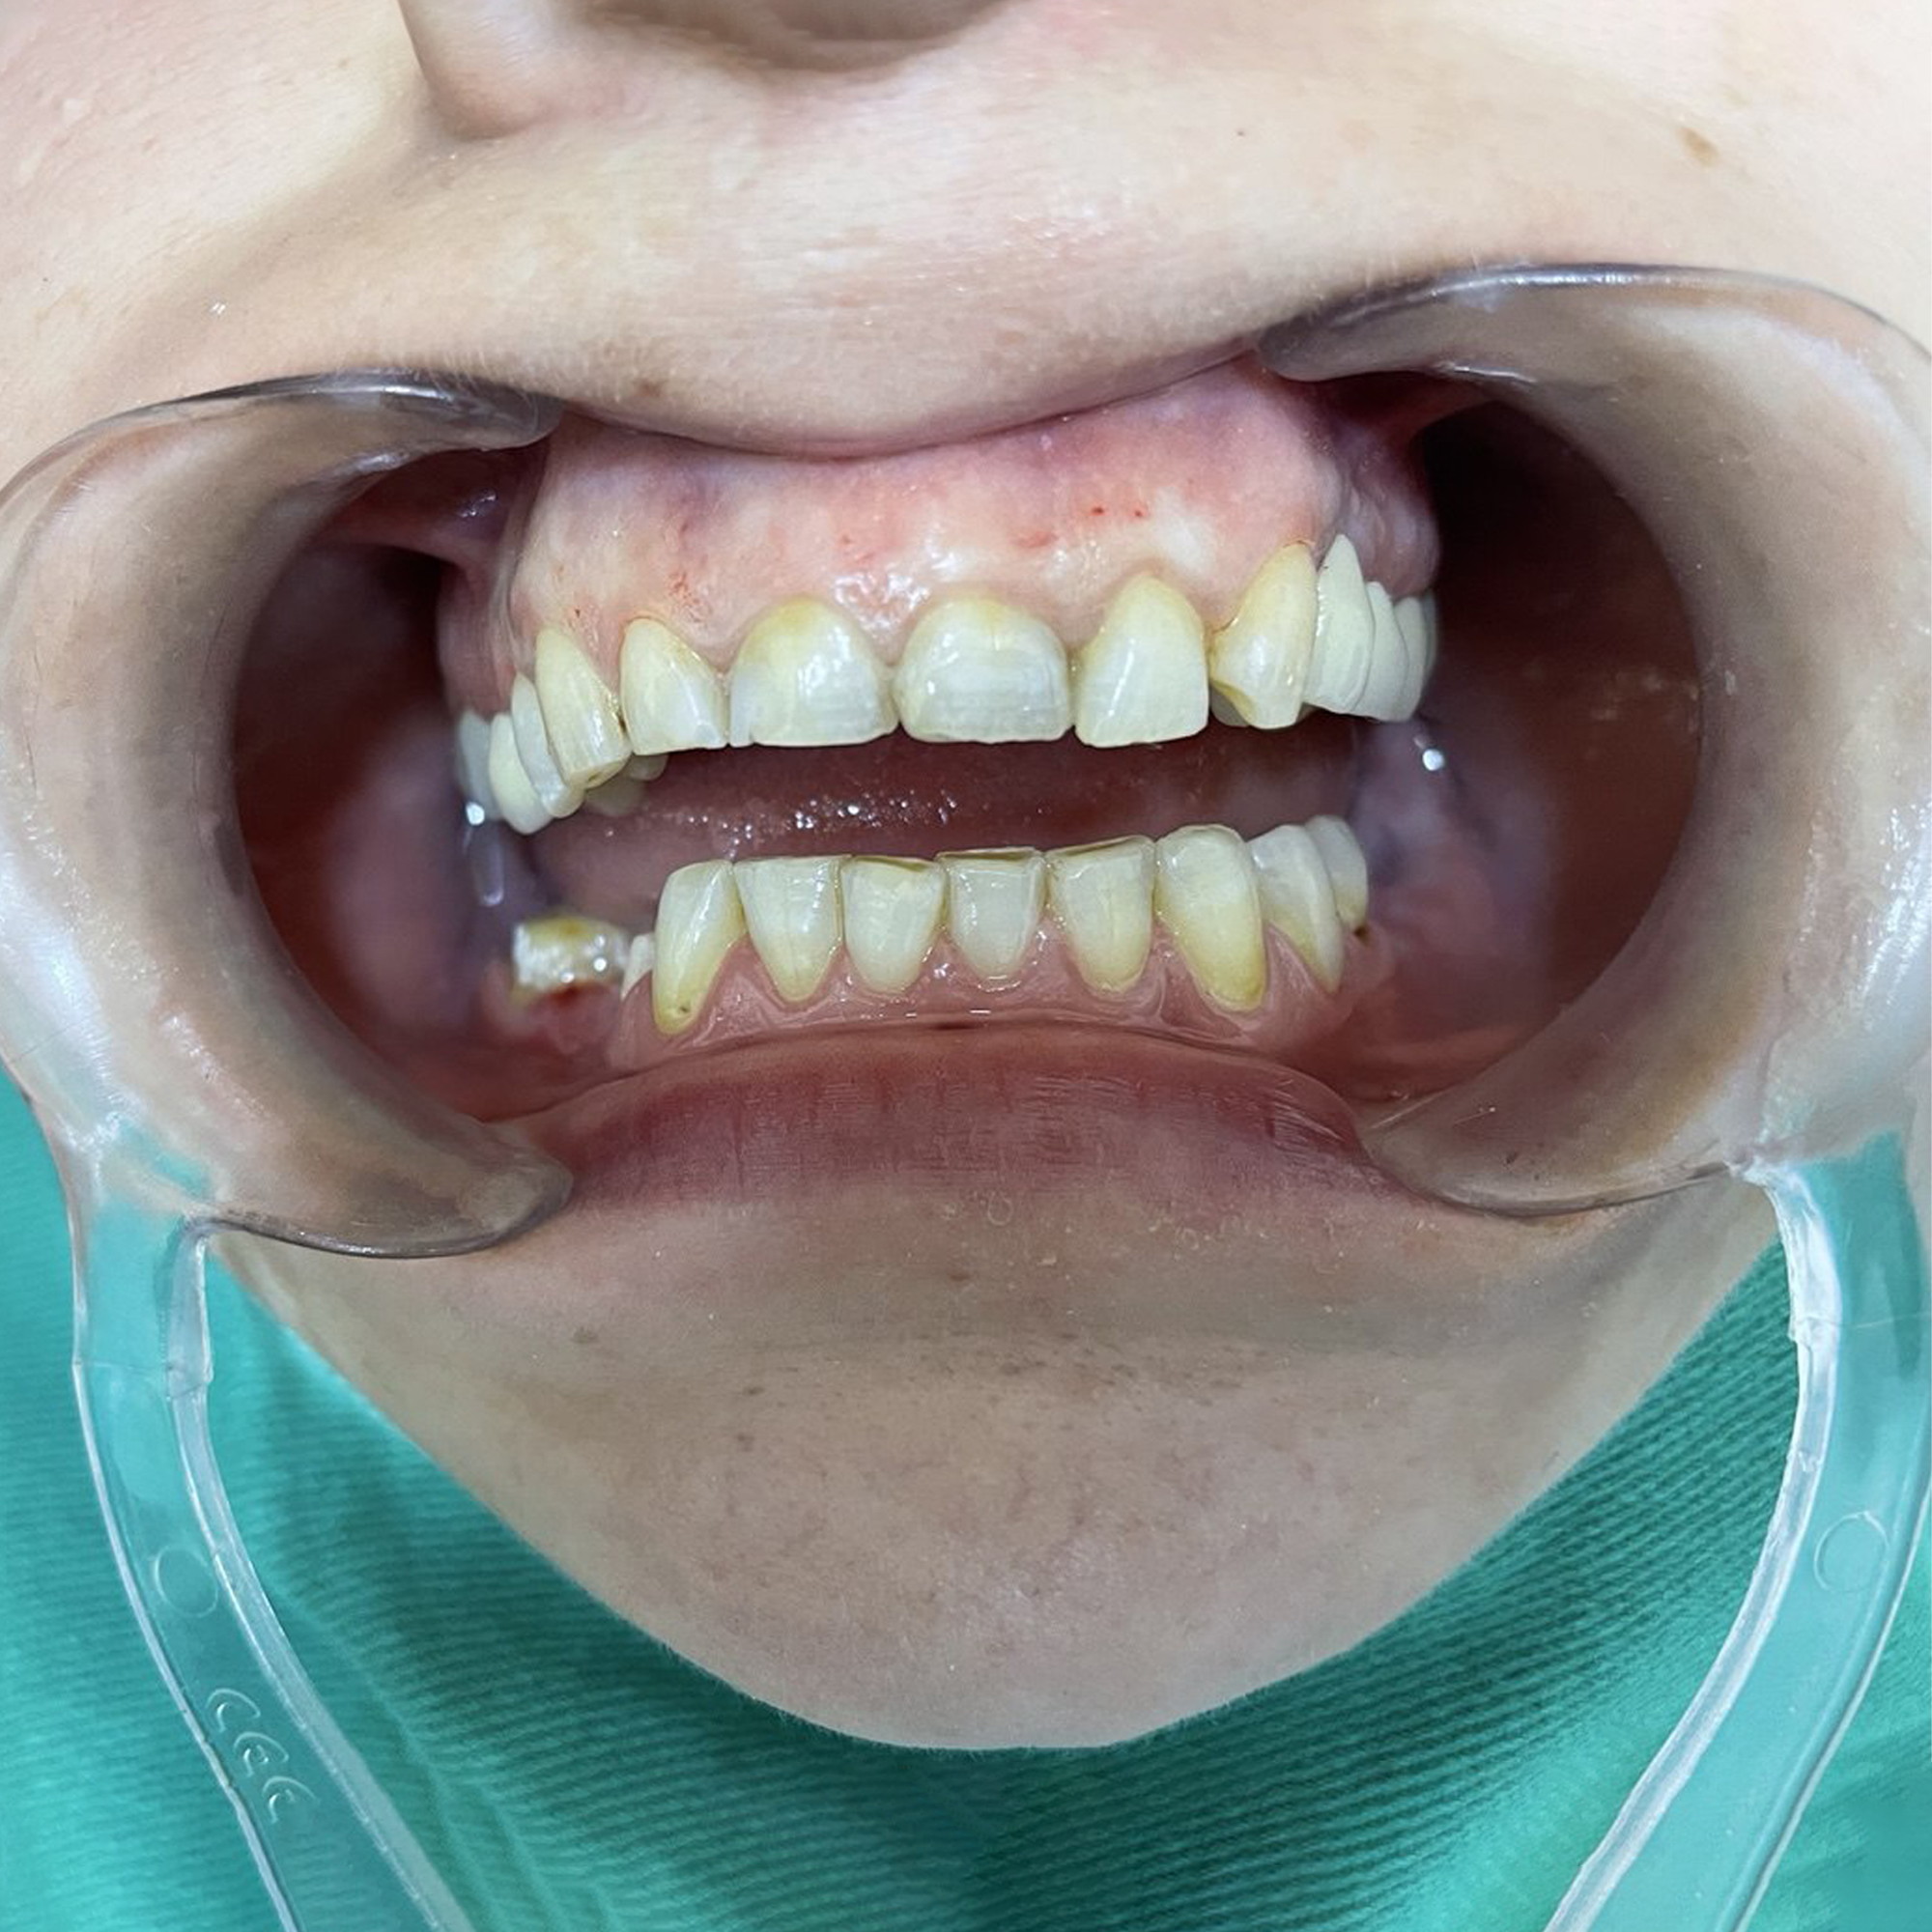

Oral Pre-Prosthetic Surgery

Perfect preparation for a flawless prosthetic fit.